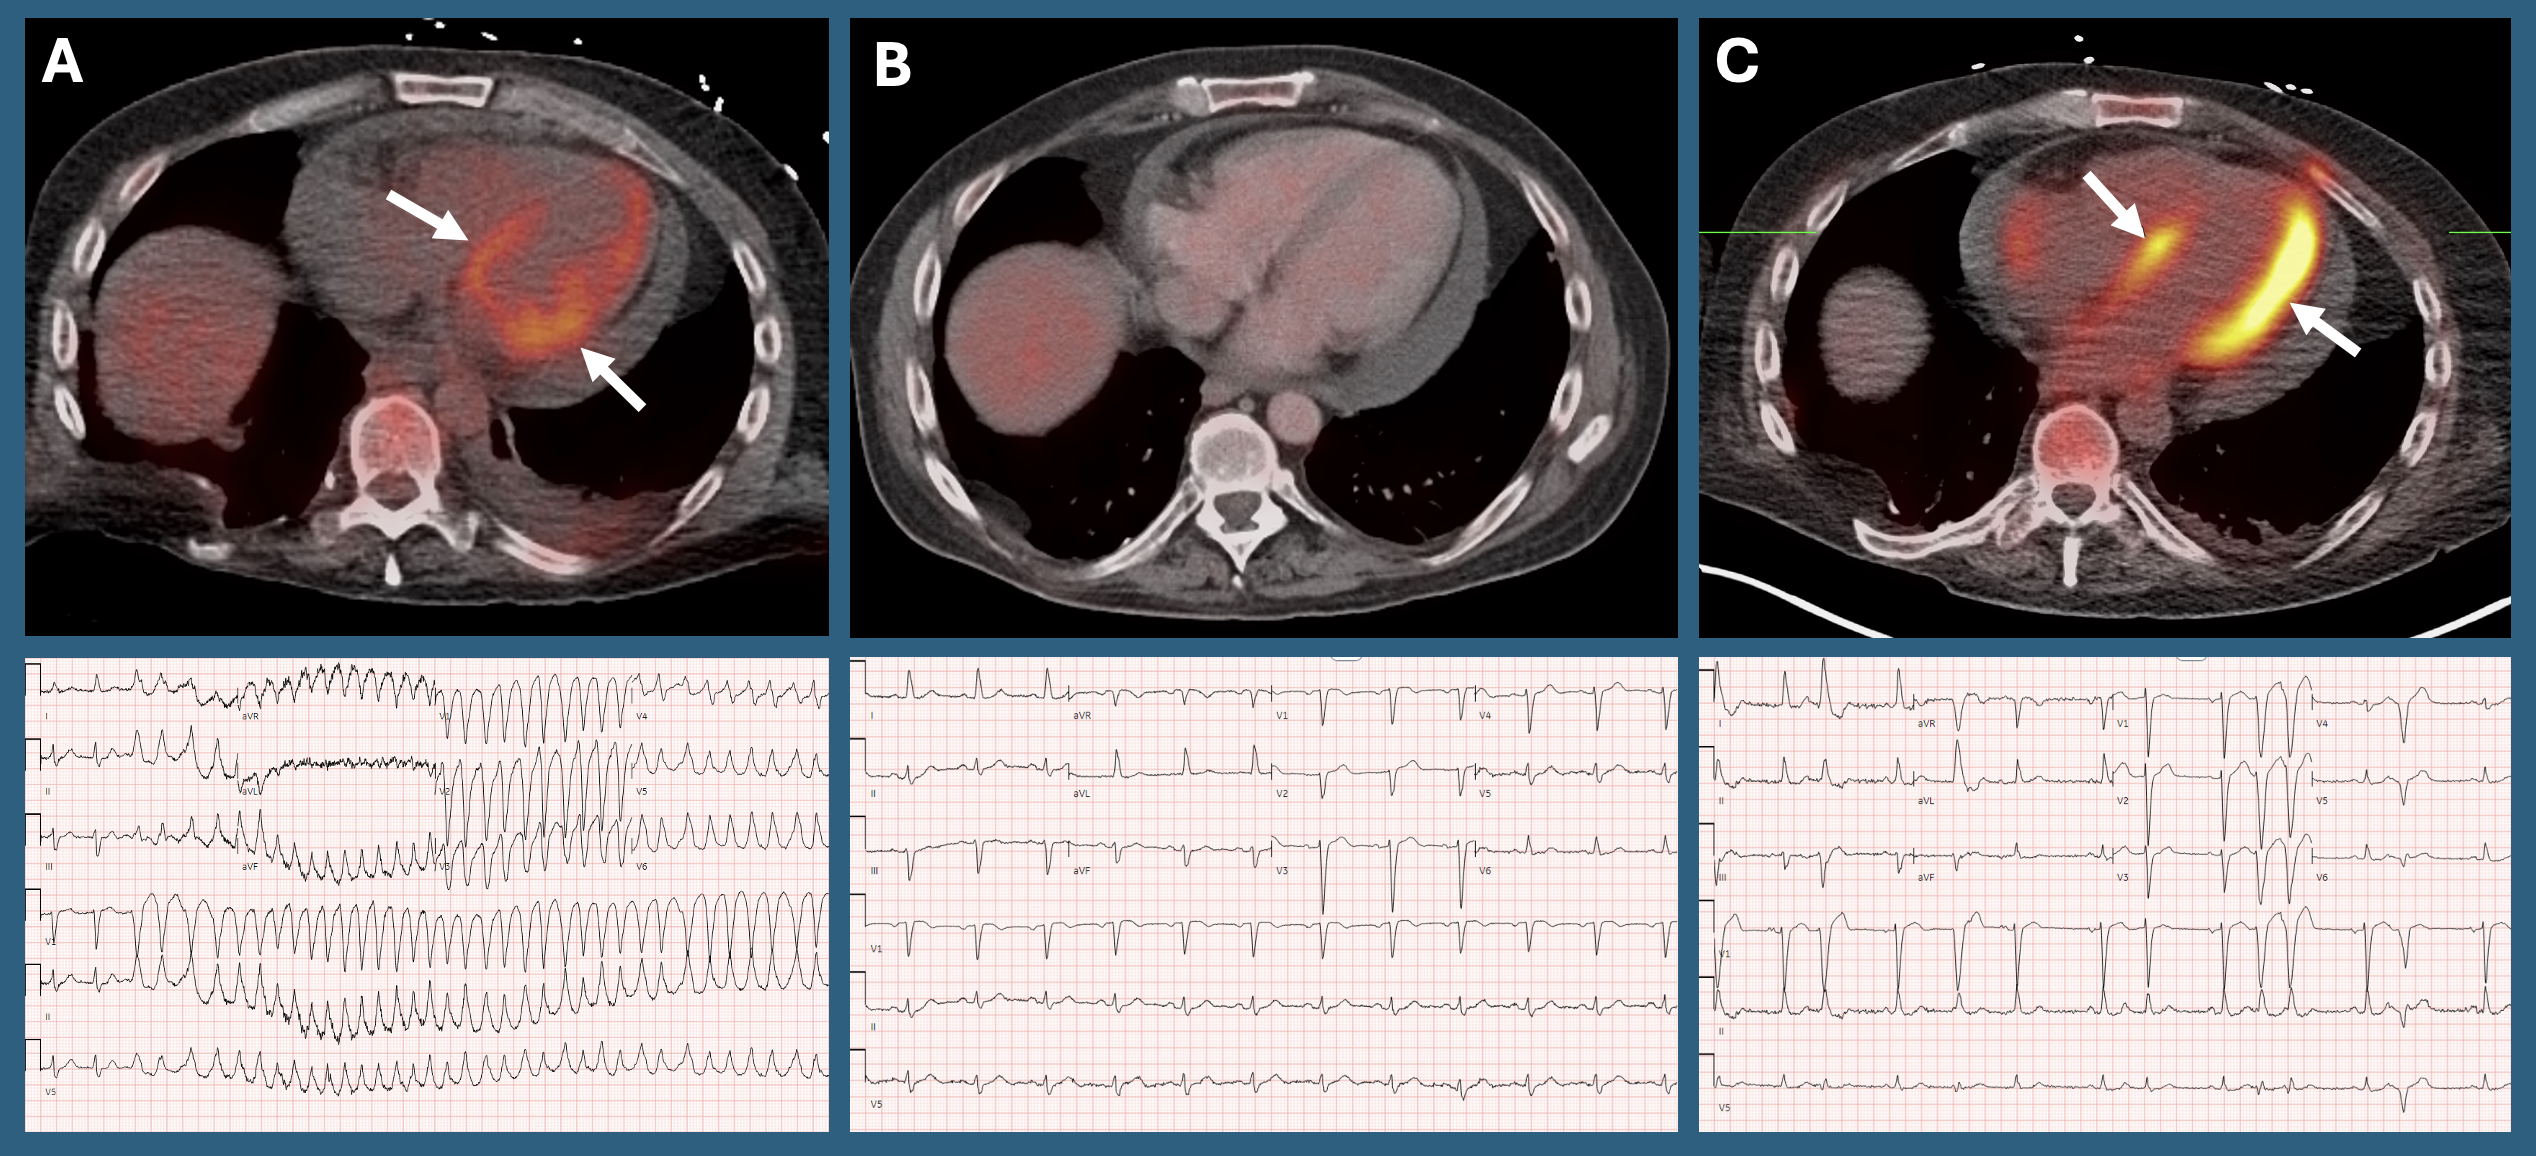

Case Report: A 51-year-old male with metastatic sarcoma on pazopanib, a VEGFR-TKI, for the past 4 years presented with 1 month of increasing palpitations and lightheadedness leading to a fall. On arrival, telemetry showed paroxysmal AF with RVR rates to 120 bpm followed by incessant runs of NSVT with rates 200-240 bpm. Initial labs included BNP 191 pg/mL and HS troponin-I 6 ng/L (<5 ng/L). Lidocaine infusion, amiodarone infusion, and metoprolol were required to reduce NSVT burden. Initial TTE revealed LVEF of 30-35% from baseline 55-60%. Coronary angiography showed no significant CAD. Cardiac MRI was negative for LGE or metastatic involvement. Cardiac PET-CT revealed moderate diffuse FDG uptake with focal enhancement suggestive of an inflammatory process. Pazopanib was stopped and the patient started on GDMT and prednisone taper for treatment of myocarditis.

At 2 months follow up, TTE revealed LVEF improved to 45-50% and ambulatory rhythm monitoring showed rare PVCs and few NSVT episodes. Repeat cardiac PET-CT revealed resolution of myocardial inflammation.

Due to sarcoma progression, the patient started on regorafenib, another VEGFR-TKI, 3 months after initial hospitalization. About 3 weeks later, he presented with frequent NSVT which required lidocaine and amiodarone infusions for arrhythmia control. Repeat cardiac PET demonstrated myocarditis recurrence. He received intravenous pulse dose steroids followed by prednisone taper and was transitioned to oral mexiletine and amiodarone with resolution of VA. Review of ambulatory rhythm monitoring 1 week following regorafenib initiation already showed 20.6% burden of ventricular ectopy and >8000 NSVT episodes.